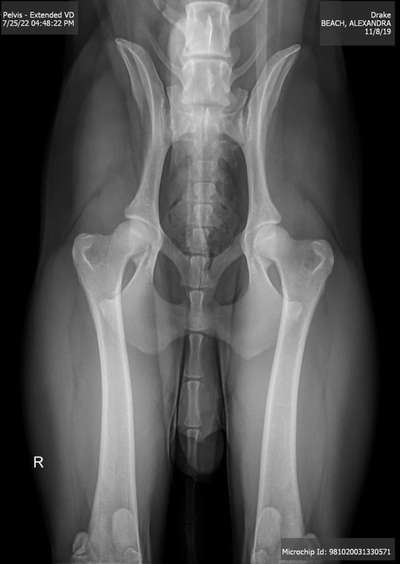

Auch interessant: Nicht sediert vs sediert, Ging wohl von leichter HD auf „fair“. Die Hüfte ist also um zwei Kategorien besser gewesen als im wachsen Zustand (amerikanisches OFA Ranking).